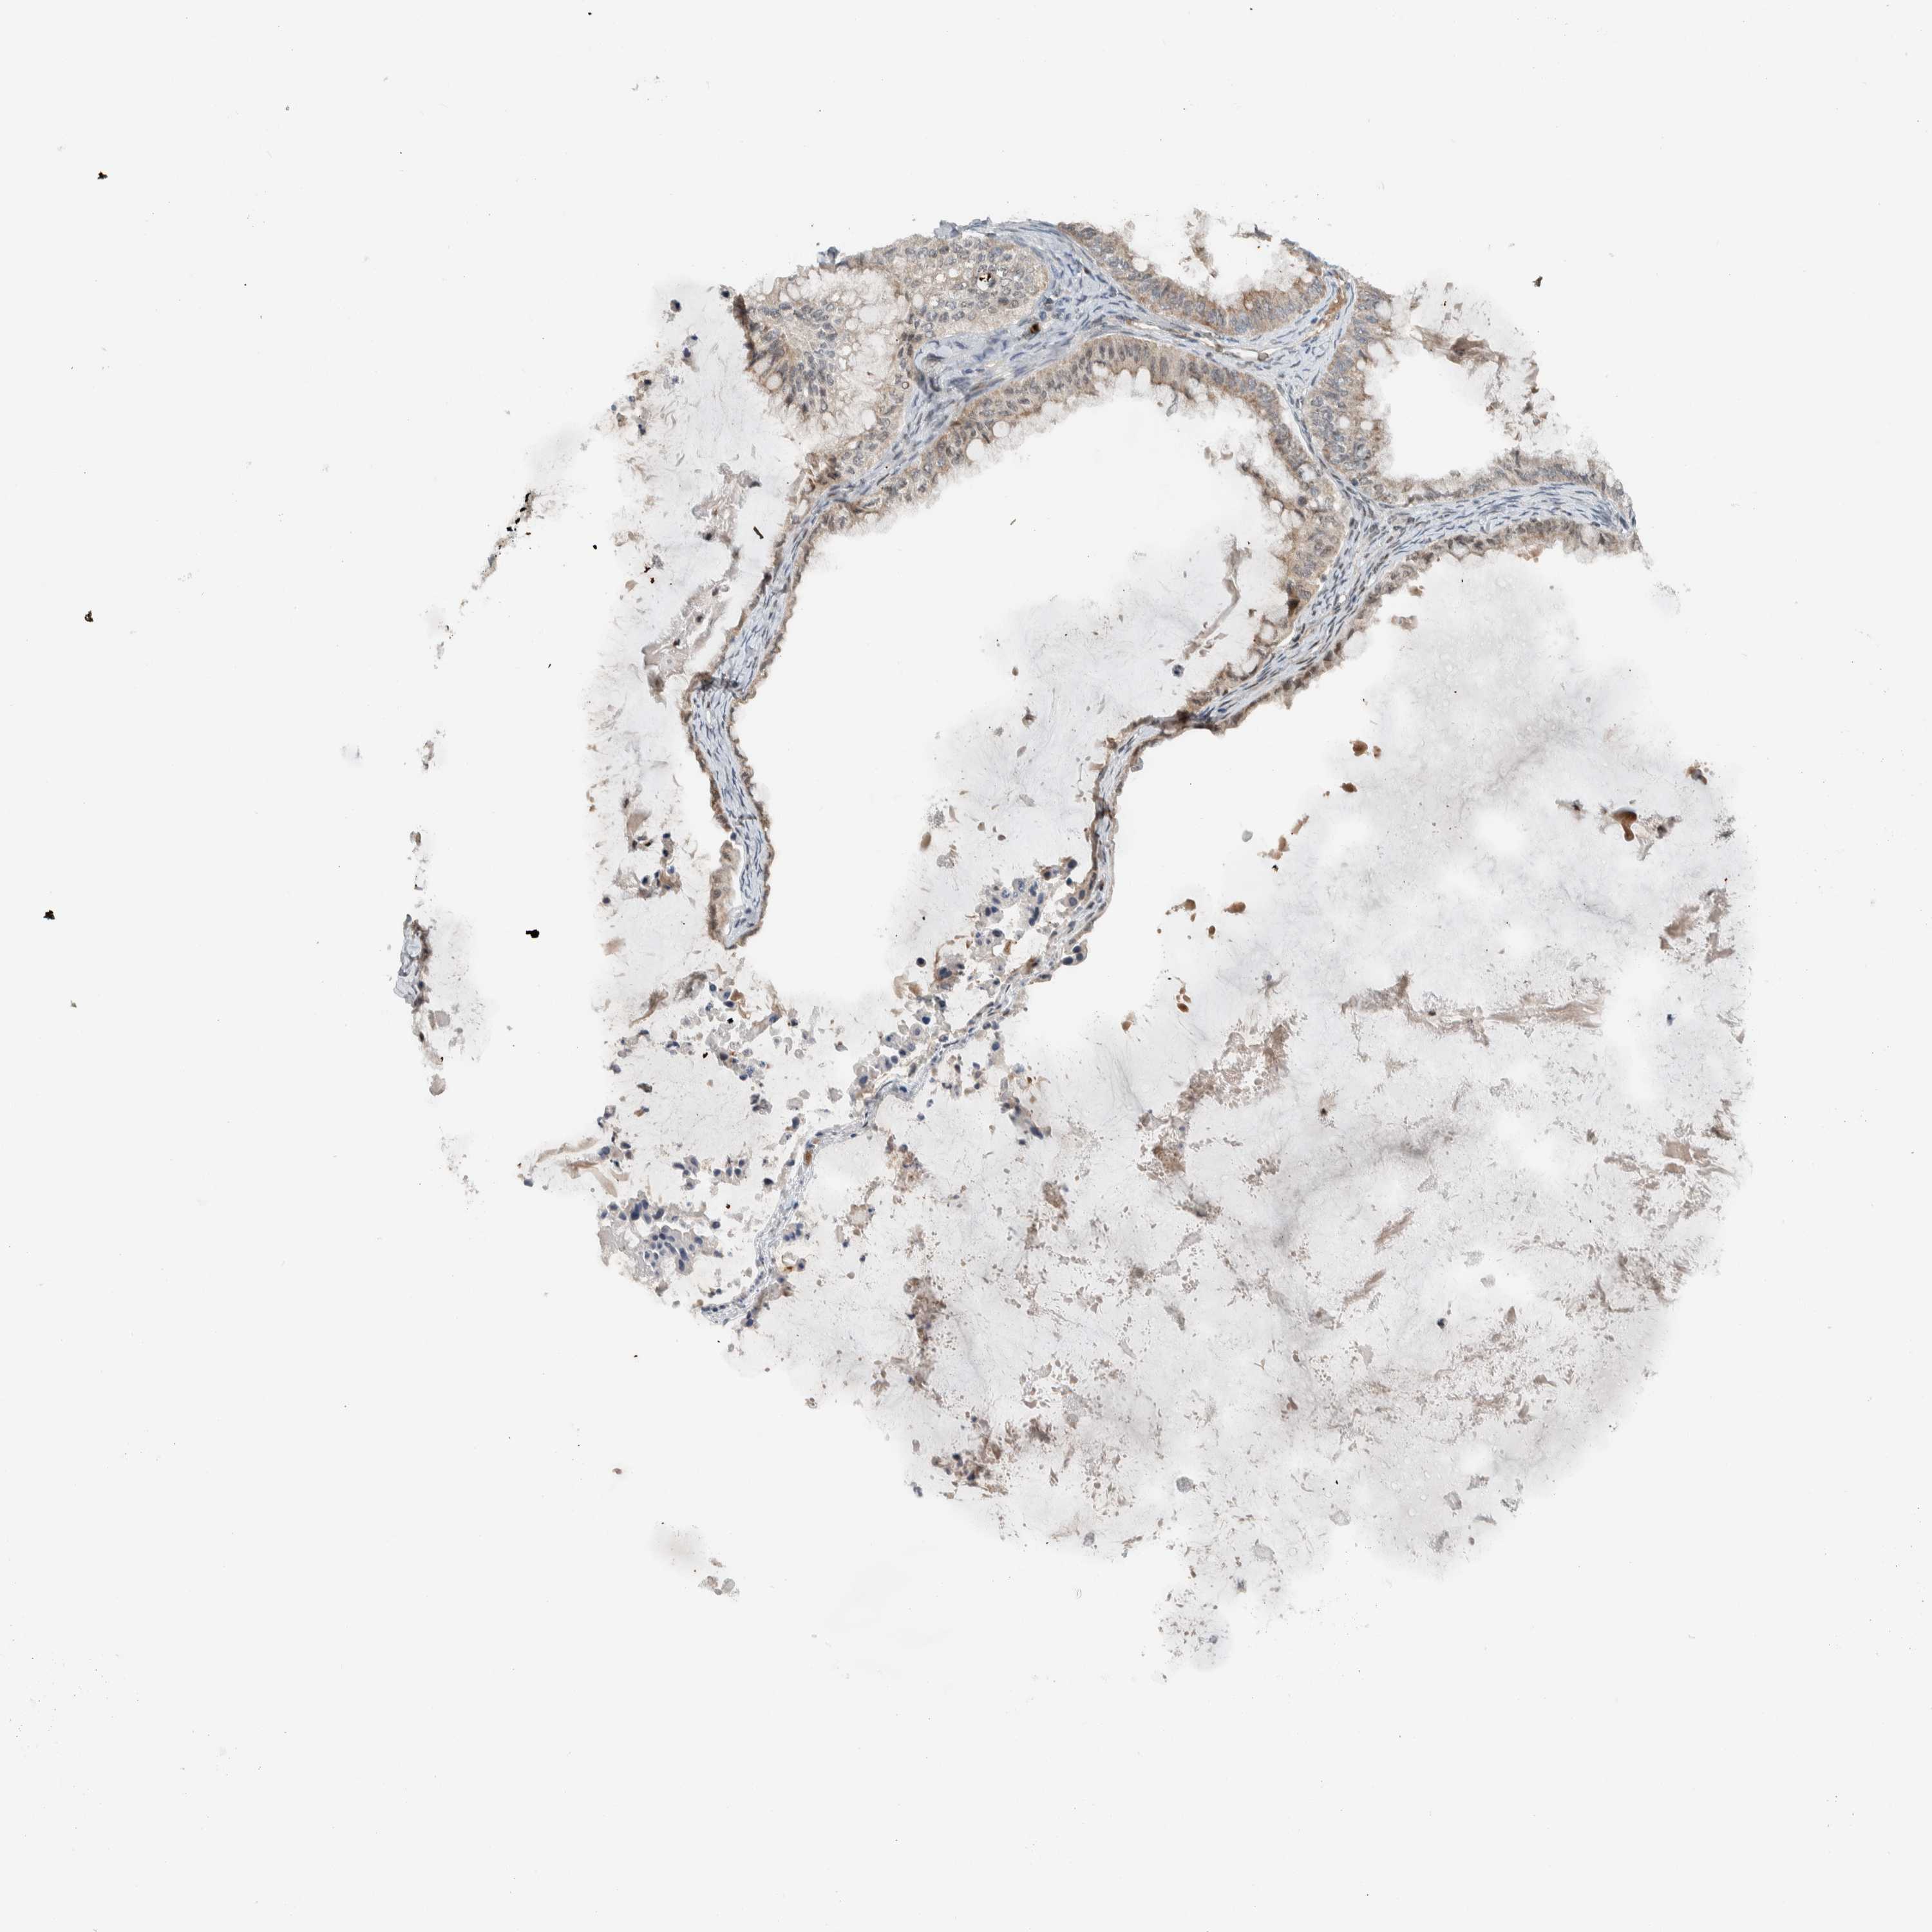

OVARIAN CANCER - Protein expressioni

A mouse-over function shows sample information and annotation data. Click on an image to view it in a full screen mode. Samples can be filtered based on level of antibody staining by selecting one or several of the following categories: high, medium, low and not detected. The assay and annotation is described here.

Note that samples used for immunohistochemistry by the Human Protein Atlas do not correspond to samples in the TCGA dataset.

Antibody stainingi

Antibody staining in the annotated cell types in the current human tissue is reported as not detected, low, medium, or high, based on conventional immunohistochemistry profiling in selected tissues. This score is based on the combination of the staining intensity and fraction of stained cells.

Each image is clickable and will lead to virtual microscopy that enables deeper exploration of all samples and also displays staining intensity scores, fraction scores and subcellular localization as well as patient and tissue information for each sample.

Antibody HPA024037

Cystadenocarcinoma, serous, NOS